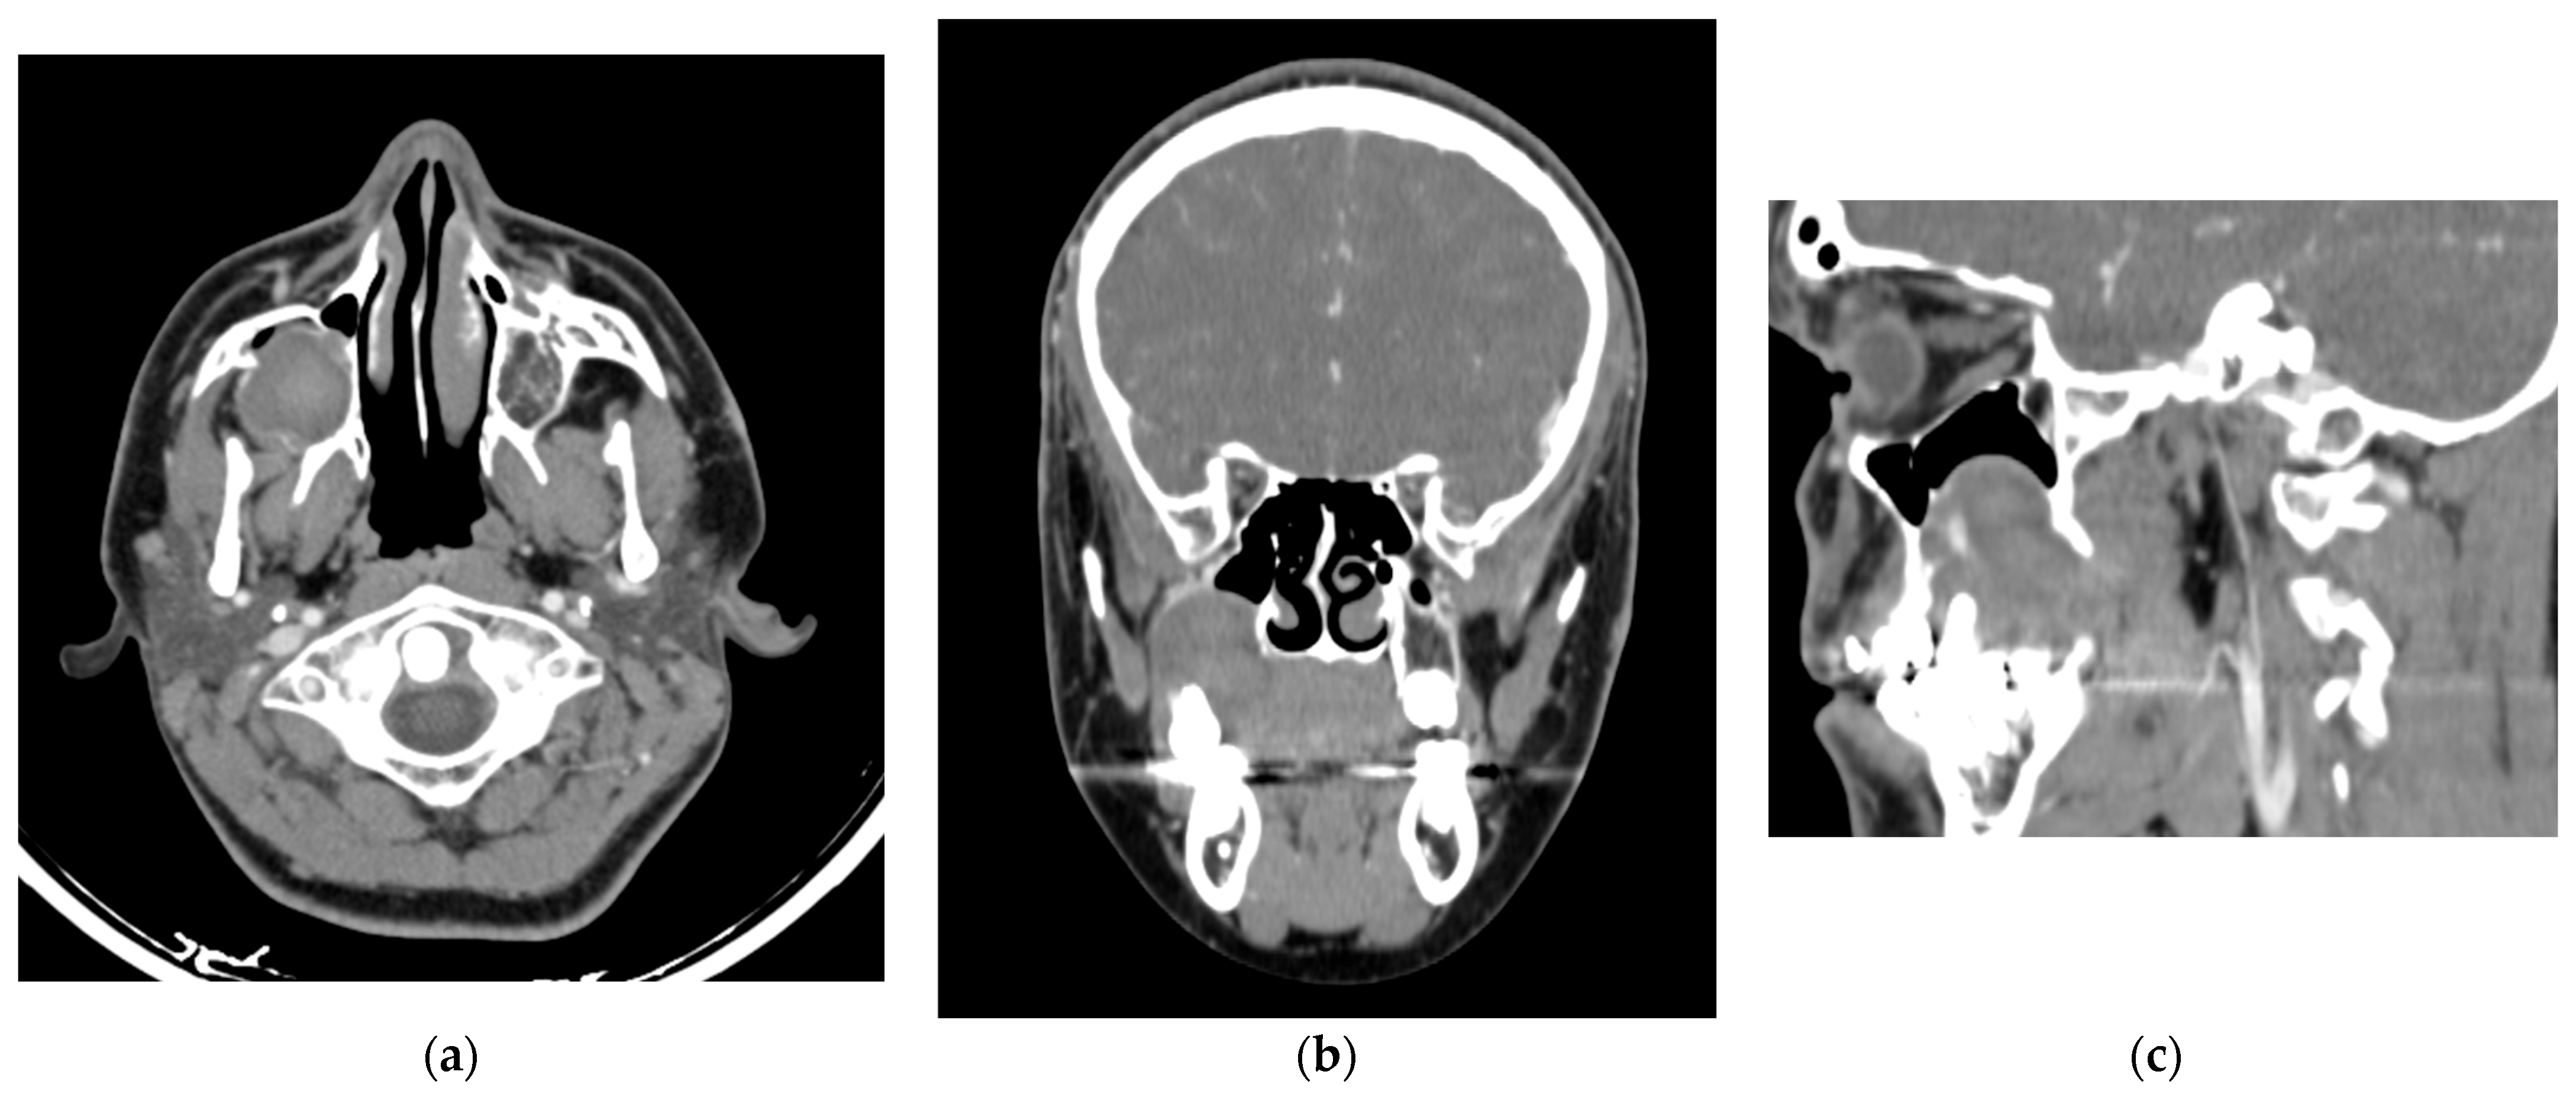

Figure 2.

Contrast-enhanced computed tomography (a) Axial slice reveals an isodense area relative to soft tissues with hyperenhancing central regions, show prominent vascularization. (b) Coronal view revealing elevation of the right maxillary sinus associated with the maxillary first molar. (c) Sagittal view illustrating in greater detail the sinus elevation and regions of hyperenhancement.